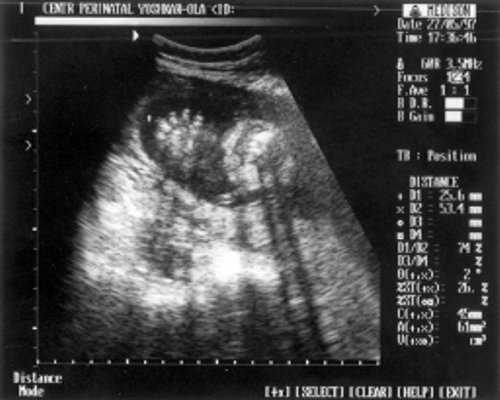

Плечевая кость = 16 мм - 14,5 нед. (рис. 3)

- Плечевая кость = 16 мм - 14,5 нед. (рис. 3)

Рис. 3. УЗИ плода - плечевая кость.